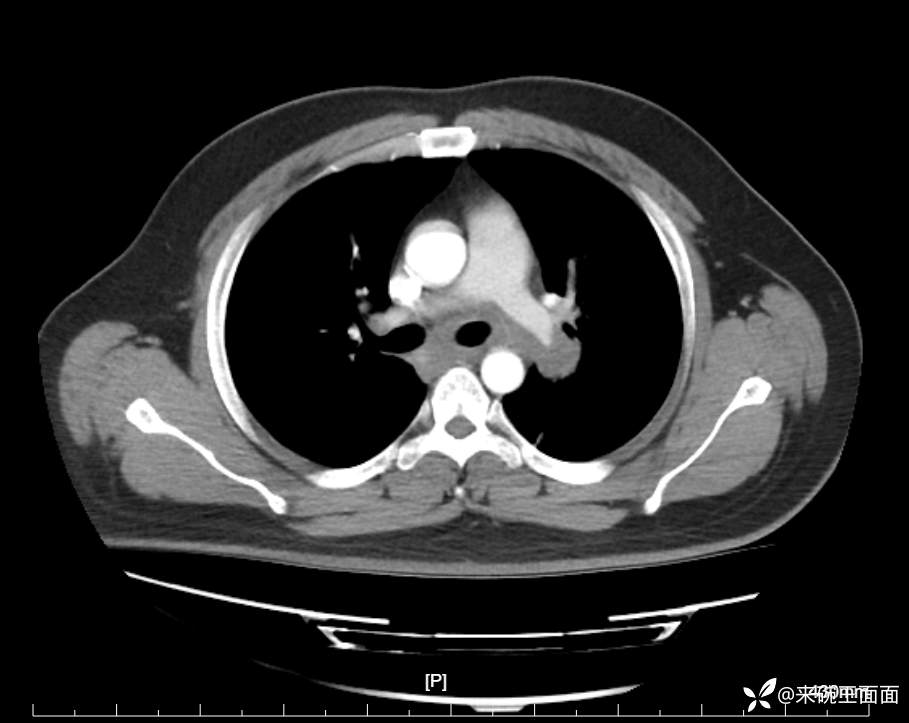

性别:男

年龄:27岁

主诉:胸闷胸痛数月余,休息后可自行缓解,无咯血症状。

个人史:数年吸烟史,具体不详。